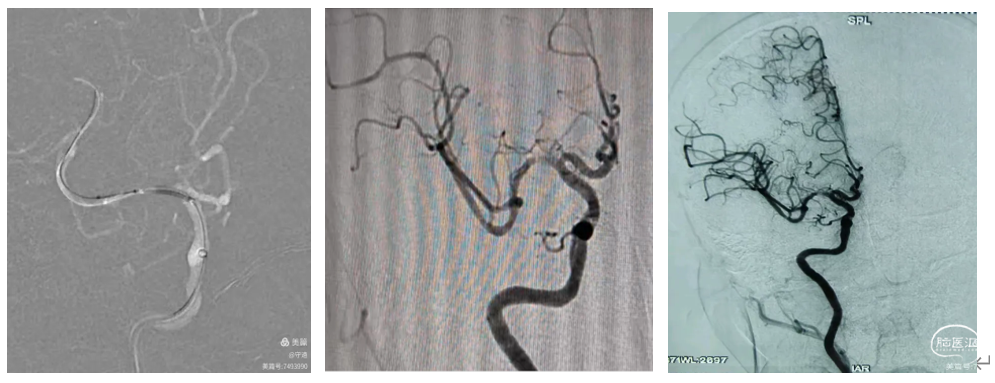

患者男性,83岁,既往房颤病史多年,以"右侧上下肢无力,言语含糊,烦燥2小时"入院。核磁显示:左侧大脑半球多发点状梗塞,老年性脑萎缩。MRA显示:左侧大脑中动脉M1起始部闭塞,未向远端供血。

Ⅱ型弓动脉,125Cm单弯同轴将8Fguiding到达颈总动脉远端建立通路。

颈内血管迂曲呈多个S弯,选择顺应性优良的ACE68抽吸导管在侧位下直接裸奔,不经意间ACE68到达C6段。但血管多个S弯折损,8Fguiding和ACE68已用尽导管长度,只能到C6段。微导丝携带微导管到M1远端,造影在真腔内,远端血管正常。

通过微导管将6*30mm Solitre支架置于M1段,静置后收扰支架尾部取栓,踹马桶抽吸ACE68抽吸导管。取出0.5Cm大小血栓和细条状血栓。

造影显示血管血流通畅达3A级,远端血管血流显影良好,未见明确逃逸征象。M1段残余狭窄约40~50%,不影响血流供应,未一期置入支架,服药观察。